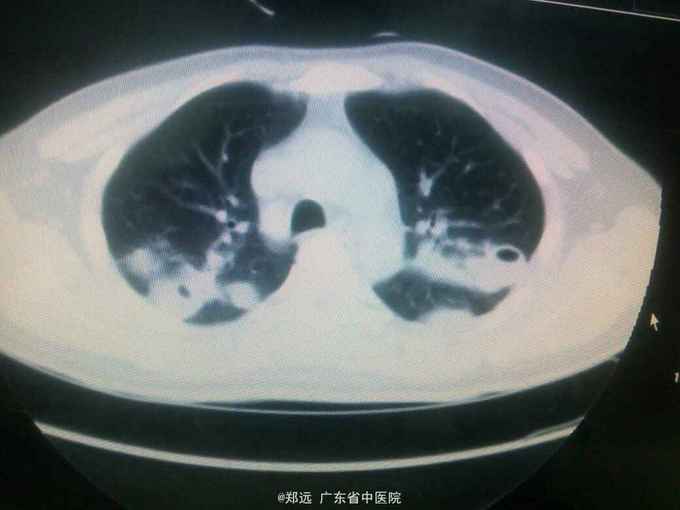

体查:双下肺湿啰音。三尖瓣区3/6级收缩期杂音。 胸部ct:双肺斑片结节影并空洞形成,左胸少量积液。血色素88克/升,白细胞11.48,中性粒81.3%,降钙素原14.84,ALT 121,AST 134.超声提示三尖瓣赘生物,三尖瓣大量返流。血培养金葡菌。

诊断:急性感染性心内膜炎,脓毒症,肺脓肿,丙型肝炎。 治疗:入院予万古霉素0.5克q6h,经治疗五日血象正常,降钙素原1.54,但仍反复高热,考虑肺脓肿合并阴性菌感染,加用头孢哌酮舒巴坦3克q12h,治疗五日仍有发热,血培养阴性,白细胞正常,降钙素原0.15,头孢哌酮舒巴坦改为美罗培南0.5克q8h,两日后无再发热,维持该方案至治疗四周后改予万古霉素0.5克q8h加美罗培南0.5克q12h继续治疗两周,复查超声提示三尖瓣熬生物较入院时缩小约三分之一,多次血培养阴性,胸部ct提示肺部炎症明显吸收予出院。出院后患者仍间发热,出院后约七周再次返院,查白细胞13.88,中性粒65.9%,血色素正常,降钙素原0.55,血培养提示溶血葡萄球菌,胸部ct示双肺多发感染灶,较前吸收,胸腔积液已吸收。予原万古霉素加美罗培南方案治疗,两日后无发热,治疗三周后多次血培养阴性,胸部ct提示肺部感染基本吸收,行三尖瓣赘生物切除并三尖瓣修补术,术中见三尖瓣后瓣瓣叶破坏严重,赘生物大小约2*1厘米。术后恢复良好,维持万古霉素加美罗培南治疗一周后改予万古霉素0.5克q8h加阿米卡星0.4克q12h治疗两周,赘生物及多次血培养阴性予出院。